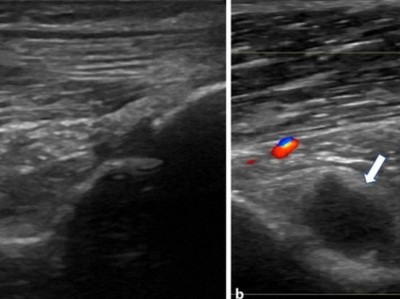

Ekzem an der Mamille ernst nehmen!

Eine 54-jährige Patientin wird mit einem seit drei Monaten bestehenden, nässenden Ekzem im Bereich der linken Mamille vorstellig. Sonografisch ergibt sich an beiden Mammae ein unauffälliger Befund. Doch die Veränderung ist Zeichen einer ernsteren Erkrankung.

Indikationen zur konventionellen Bildgebung am Ellenbogen/© Rentschler V et al. / all rights reserved Springer Medizin Verlag GmbH, Transrektale MRT/© Springer Medizin, Osteoporotisch bedingte Sinterungsfrakturen der Wirbelsäule/© L. Heuchemer, D. Emmert, T. Bender et al./Springer Medizin Verlag GmbH, Person isst eine Krankenhaus-Mahlzeit/© gballgiggs / Stock.adobe.com (Symbolbild mit Fotomodell), Springer Medizin Podcast - Stürze im Alter/© Gatz M et al / all rights reserved Springer Medizin Verlag, Mann erhält einen CT-Scan /© Mark Kostich / stock.adobe.com (Symbolbild mit Fotomodell), Person hält zwei Tabletten in der Hand/© AsiaVision / Getty Images / iStock (Symbolbild mit Fotomodell), Fallbeispiel Röntgenaufnahme des Thorax in zwei Ebenen/© Reinke L. et al. / all rights reserved Springer Medizin Verlag GmbH, Frau bei Knochenmineraldichte-Messung/© gelmold / stock.adobe.com (Symbolbild mit Fotomodell), Senior im Krankenhausbett mit gebrochenem Fuß/© Mat Hayward / Stock.adobe.com (Symbolbild mit Fotomodell), Abb - Röntgenaufnahme der linken Hüfte anterior-posterior/© K. M. Peters, Ekzem an der Brustwarze/© T. Jansen, Auch der Knochen leidet bei Diabetes - oft schon im mittleren Lebensalter/© Trueffelpix / stock.adobe.com, Ultraschalllängsschnitt der Fossa olecrani/© Springer Medizin Verlag GmbH, Search Icon, Kind streckt sich freudig, Mutter sitzt und lacht/© BioMarin